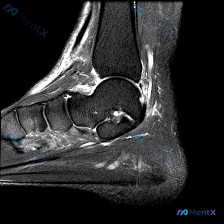

踝关节MRI看到多部位高信号,别只想到足底筋膜炎!

今天分享一例踝关节矢状位T2序列MRI的读片病例,整理了完整分析思路,和大家一起讨论。 病例影像基本信息 检查部位:踝关节MRI-T2序列-矢状位 可见解剖结构:胫骨远端、距骨、跟骨及部分跗骨 核心影像异常表现 1. 骨组织:距下关节跗骨窦区可见高信号影,距下关节面上方伴异常液体信号;跟骨内部靠近跖...